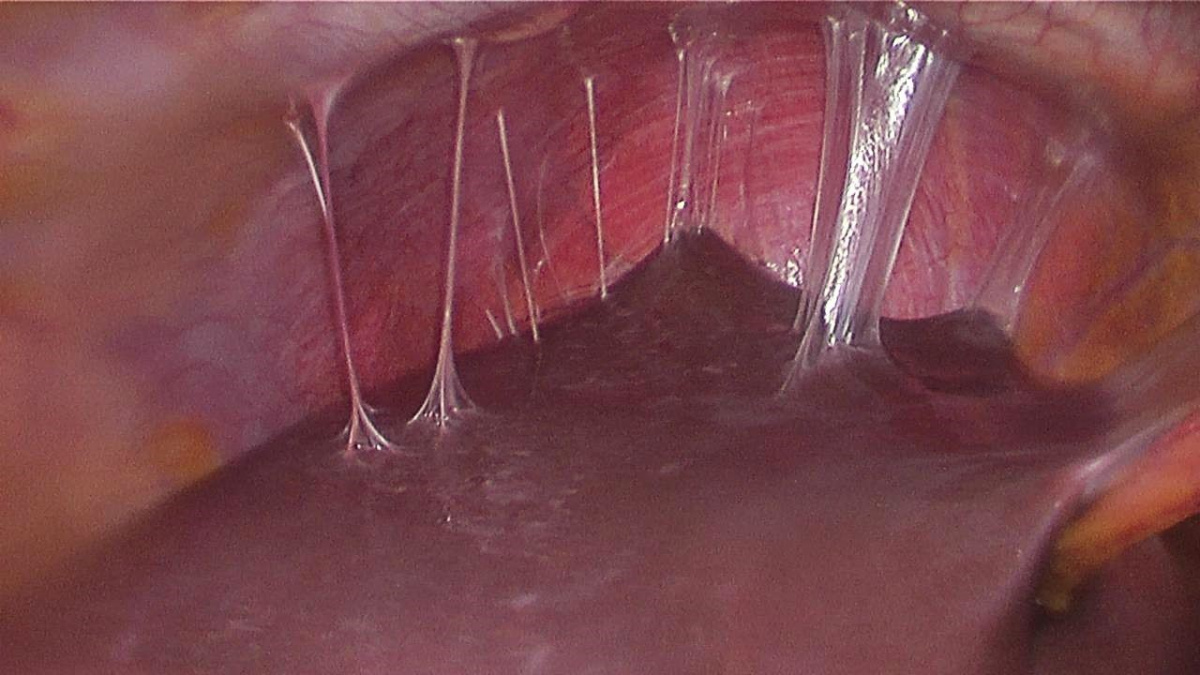

Fıtık onarımının dünya çapında en yaygın cerrahi prosedürlerin başında geldiğine işaret eden Prof. Dr. Esra Karaca, her yıl yaklaşık yirmi milyon hastanın fıtık gelişimine bağlı olarak ameliyat edildiğini açıkladı. Karın duvarında oluşan defektin, mesh adı verilen bir tıbbi tekstil materyali implante edilerek onarılmasının da bu alanda yapılan en yaygın cerrahi müdahalelerden birisi olduğunu söyleyen Prof. Dr. Esra Karaca; “Bununla beraber, kullanılan meshler ciddi adezyonlara neden olmaktadır. Daha önce fıtık ameliyatı olmuş hastaların %90'ından fazlasının ameliyat sonrası adezyon semptomları gösterdiği tespit edilmiştir. Adezyonlar ise, kronik karın ağrılarına ve iç organlarda ölümcül tıkanıklıklara yol açabilmektedir. Yeni ürünler denenmesine rağmen, post-operatif adezyon henüz başarıyla önlenememiştir. BUÜ Tıp Fakültesi Hastanesi’nden Türkiye ile ilgili bir projeksiyon yapılarak, ülkemizde bir yılda kullanılan fıtık mesh sayısının 100 bin civarında olduğu sonucuna varılmıştır. Bu nedenle; proje kapsamında geliştirilecek başarılı bir kompozit meshin, yurt dışından mesh ithalatını önemli oranda azaltacağı öngörülmektedir” açıklamasında bulundu.

Karaca ayrıca projede, karın fıtıklarının onarımında kullanılmak üzere çörek otu yağı içeren anti-adezyon özellikli nanolifli yüzey ile takviyelendirilmiş PP örme mesh yapıların geliştirilmesi ve kompozit meshlerin fıtık onarımı ve adezyon önleme performansının in vitro ve in vivo çalışmalarıyla değerlendirilmesini amaçladıklarını da sözlerine ekledi.